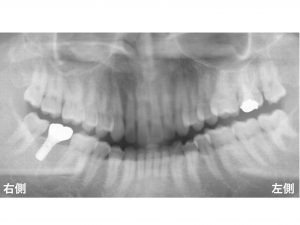

以下が初診時です。

下顎右側奥から2番目が欠損している患者様です。

このようなケースの場合、

できればブリッジは避けたいです。

その理由として、

欠損の前後の歯は、

なにも削ってないない健康な歯です。

以下が治療後です。